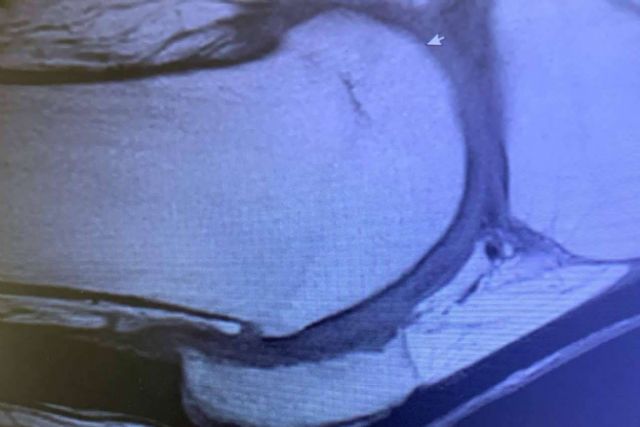

Lo que más afecta a la artrosis son las articulaciones que se someten a carga o estrés repetidos, sobre todo la rodilla y la cadera. Al saltar o simplemente al subir escaleras, algunas zonas de la rodilla soportan más de 10 veces el peso del cuerpo.

También se suelen afectar otras articulaciones pequeñas como las del cuello, en relación con malas posturas, o las de las manos, en trabajadores manuales. Lo que se nota es que crujen las rodillas al subir las escaleras, que hay que “calentar” para mover bien las articulaciones; después se nota dolor leve o rigidez que dificulta ciertos movimientos, pérdida de agilidad…